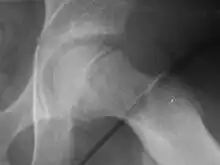

| Radiogram of slipped capital femoral epiphysis |

Klein's line is a virtual line that can be drawn on an X-ray of a child's hip parallel to the upper edge of the femoral neck. If the line does not intersect with the outermost part of the femoral head 's ball-like end, the diagnosis of a slipped capital femoral epiphysis (SCFE) is confirmed.[1]